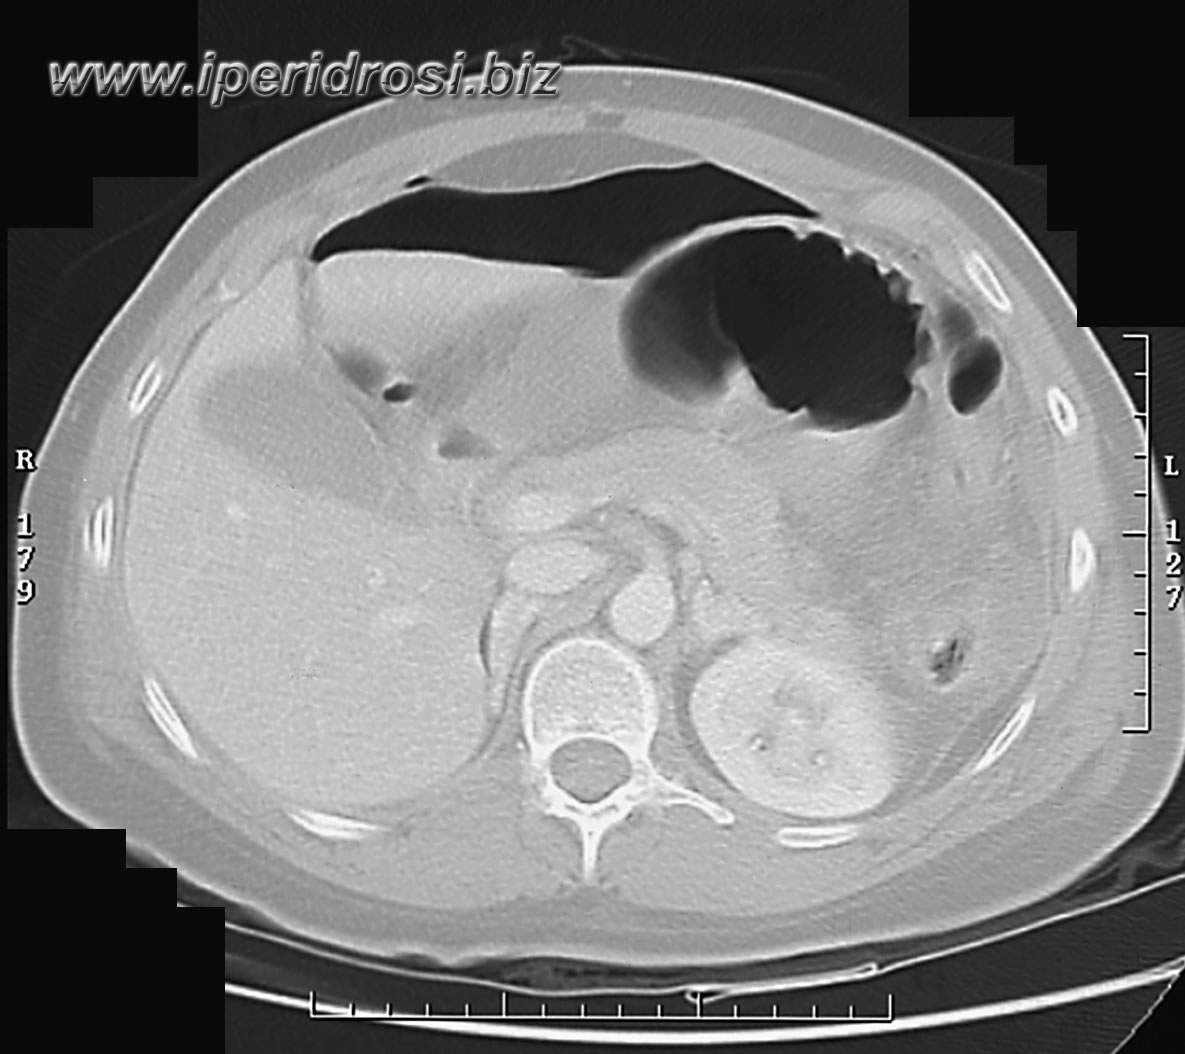

Addome: abbondante versamento addomino-pelvico diffuso con falda aerea piuttosto abbondante all'addome superiore. Rene a ferro di cavallo con cisti parapieliche a sinistra. Distensione del colon da meteorismo ed ispessimento delle pareti intestinali con iperemia di numerose anse.